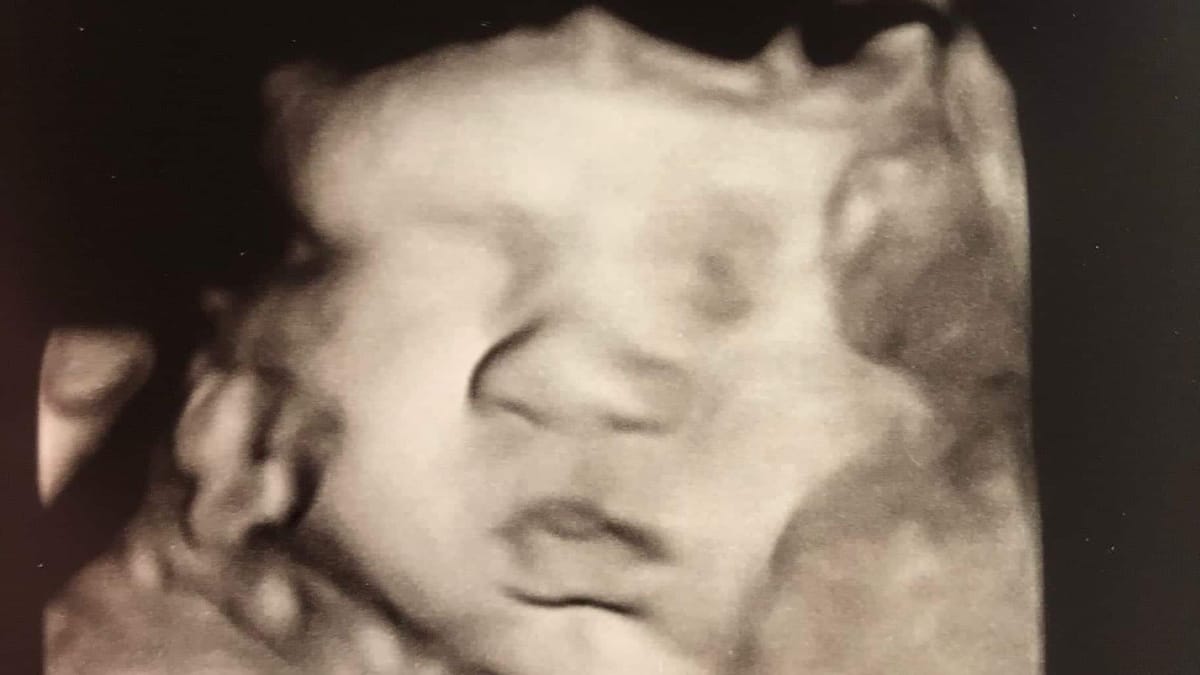

My wife and I said and thought all of the above. And then she got pregnant. Sure, we planned—as much as a human with extremely limited virtually zero control over the substantial events of life can plan such things.

Our daughter was born while I was essentially between jobs and starting a new business because applying to hundreds of jobs hadn't panned out. Sixteen months later, our son was born. And then 15 months after that, we had our youngest son.